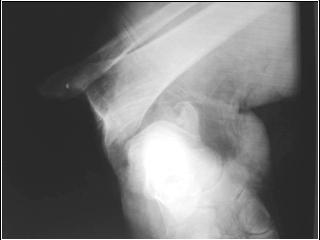

Sometimes you know a fracture is

an open fracture (even without

clinical evaluation!!!)